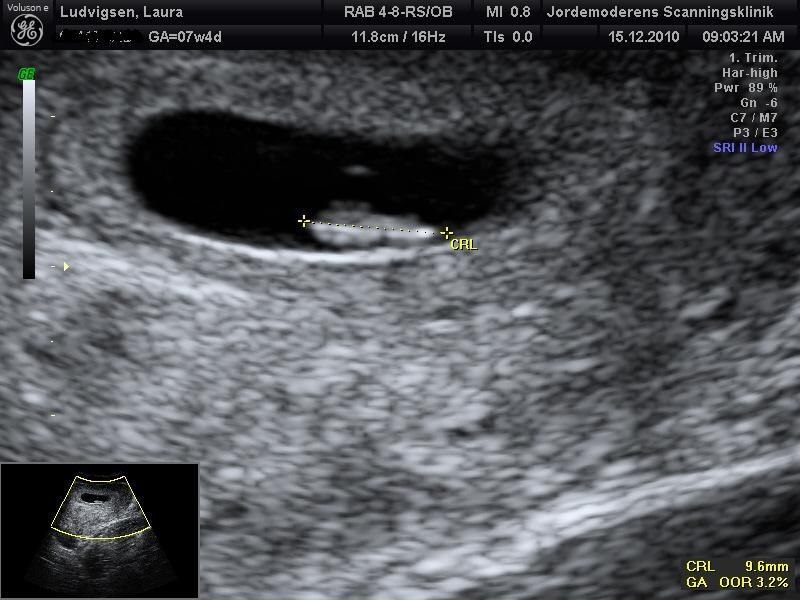

fik bekræftet hjerteblink

!som jeg gik meget op i .. gav 825 kr.

men det var meget vigtigt for mig.. ville se ikke tro